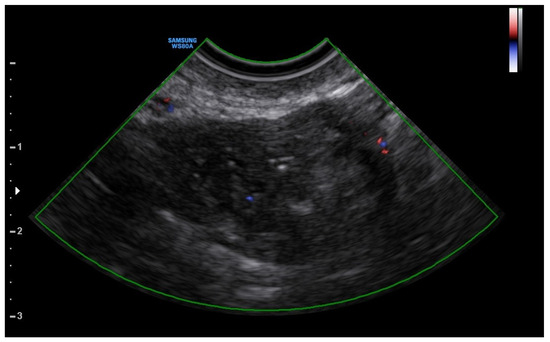

A 25-year-old woman, with a history of left tubal laparoscopic salpingectomy for an ectopic pregnancy, sought medical attention at the hospital’s emergency department after an episode of vaginal bleeding at 5 + 6 weeks of amenorrhea. At Day-1, her β-hCG was 2528 mUI/mL but a transvaginal ultrasound scan (TVUS) showed no clear evidence of pregnancy. Therefore, the patient was admitted with a diagnosis of pregnancy of unknown location (PUL). Upon admission, the patient was clinically and hemodynamically stable and did not report any pain or active bleeding. Serial measurement of her β-hCG in the following days was consistent with a suboptimal growth (3696 at Day-2, 5898 at Day-4, 10,984 at Day-7). Repeated TVUSs failed to show sure evidence of pregnancy until Day-7, when an intramural vascularized mass of 27 × 8 × 20 mm, with a gestational sac of 7 mm, a yolk sac and a 2 mm embryo with a heartbeat, was detected (Figure 1). Pelvic nuclear magnetic resonance (NMR) performed at Day-7 confirmed the presence of an intramyometrial T2-hypointense signal alteration of 20 mm in the right cornual area, surrounded by ectasic vessels, suggestive of interstitial pregnancy (Figure 2). After thorough counselling, a conservative management was proposed and accepted by the patient. The patient was administered a single oral dose of mifepristone 600 mg in combination with multidose systemic MTX 72 mg on days 0, 2, 4 and 6 from diagnosis. Follow-up by TVUS and β-hCG measurement was carried out. By Day-15, β-hCG reached a plateau and started reducing. A TVUS confirmed the termination of the pregnancy by involution of the gestational sac and the presence of the embryo with the disappearance of the fetal heartbeat. After 22 days from treatment, while the pregnancy was disappearing, in the same site, TVUS showed the appearance of a myometrial tubular hypoechoic region of 37 × 38 mm with an intensely vascular and multidirectional flow. Spectral Doppler ultrasound showed a low-resistance, high-velocity (peak systolic velocity of 128 cm/s) flow pattern, suggestive of uterine arteriovenous malformation (AVM) in the location of the previous interstitial pregnancy (Figure 3). The patient remained asymptomatic. To avoid menstrual bleeding and minimize the risk of metrorrhagia, a depot 3.75 mg shot of a GnRH analogue was administered every 28 days for 4 months. Considering the desire to preserve the fertility of the patient, the absence of guidelines for the treatment of AVM and the good results presented in the literature on uterine artery embolization as a conservative treatment, we performed a right uterine artery embolization, with sonographic resolution of the AVM within 3 months (Figure 4). We accessed the right common femoral artery and a 5-Fr introducing an angiographic sheath was placed. A 5-Fr Cobra catheter (Cook, Bloomington, IN, USA) was used to perform nonselective angiograms of the internal iliac arteries in order to achieve a general understanding of the vascular anatomy; the right internal iliac artery was selected after creating a Waltman loop with the Cobra catheter. The right uterine artery was selected using a microcatheter ranging from 2.0 to 2.4 Fr. As embolic materials, polyvinyl alcohol particles were used (Contour; Boston Scientific, Cork, Ireland). The rescue treatment had no complications. We present an unpublished case of interstitial pregnancy in a hemodynamically stable woman at an early gestational age successfully treated with medical therapy using MTX and mifepristone, who developed a peculiar complication.

Figure 2. Pelvic nuclear magnetic resonance confirming the presence of an intramyometrial T2-hypointense signal alteration of 20 mm in the right cornual area.